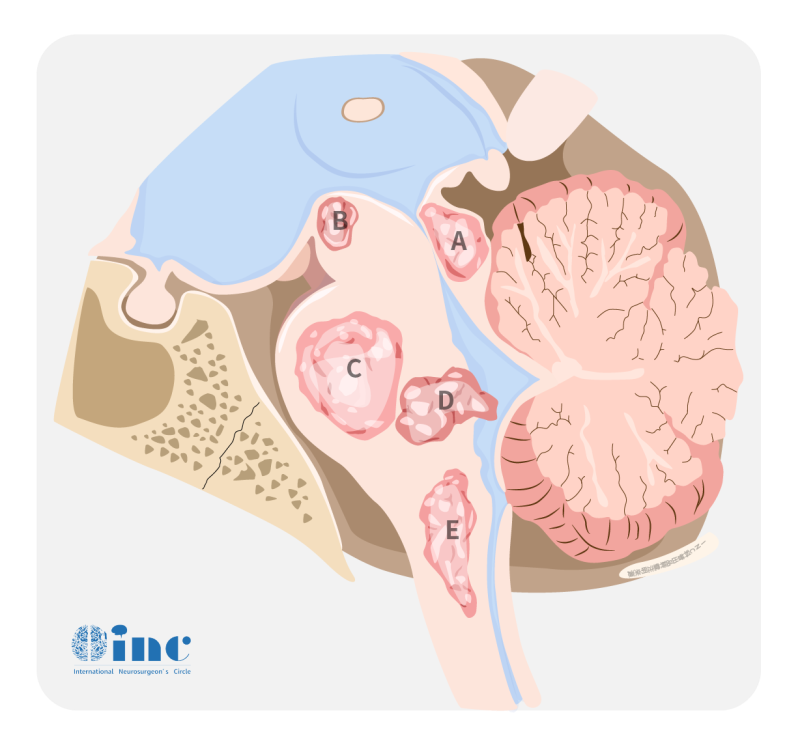

丘脑是位于脑干上方的成对结构,是身体和大脑皮层...

2022-03-01 15:30:51